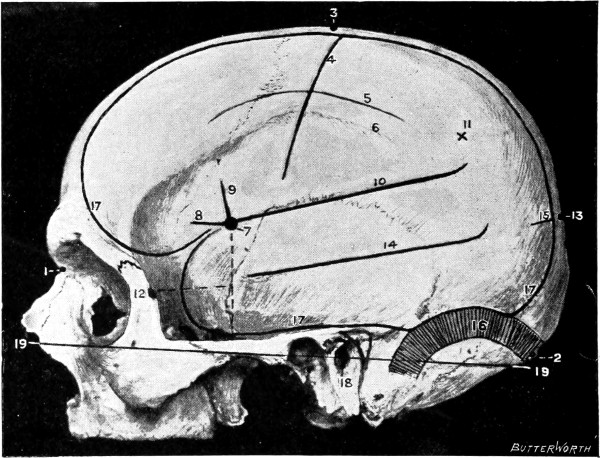

Fig. 1. Cranio-cerebral Topography. 1, The nasion; 2, The inion; 3, The mid-point between nasion and inion; 4, The Rolandic fissure; 5, The superior temporal crest; 6, The inferior temporal crest; 7, The Sylvian point; 8, The anterior horizontal limb of the Sylvian fissure; 9, The vertical limb of the Sylvian fissure; 10, The posterior horizontal limb of the Sylvian fissure; 11, The parietal prominence; 12, The malar tubercle; 13, The lambda; 14, The first temporo-sphenoidal sulcus; 15, The external parieto-occipital sulcus; 16, The lateral sinus; 17, 17, 17, The level of the base of the cerebrum; 18, The external auditory meatus; 19, 19, Reid’s base-line. (Reproduced, by the permission of Mr. H. K. Lewis, from the author’s work on ‘Landmarks and Surface-markings’.)

Fig. 2. Cranio-cerebral Topography. 1, 1, Reid’s base-line; 2, 2, A line parallel to the above at the level of the supra-orbital margin; 3, The middle meningeal artery; 4, The anterior branch; 5, 5, 5, The three sites for trephining; 6, The posterior branch; 7, The site for trephining; 8, The point for trephining to reach the descending horn of the lateral ventricle; 9, The lateral sinus; 10, The inion; 11, The mastoid process; 12, Macewen’s suprameatal triangle; 12a, The mastoid antrum; 12b, The facial nerve; 13, The suprameatal and supramastoid crests; 14, 14, The temporal crest; 15, The temporal fossa; 16, The external angular frontal process; 17, The tendo-oculi attachment; 18, The lachrymal groove. (Reproduced, by the permission of Mr. H. K. Lewis, from the author’s work on ‘Landmarks and Surface-markings’.)

The middle meningeal artery.

This artery is given off from the internal maxillary; after a short extra-cranial course it enters the skull through the foramen spinosum, and soon divides into two main terminal branches. The site of division corresponds to a point situated just above the centre of the zygoma.

The anterior branch passes at first in a forward and upward direction towards the anterior inferior angle of the parietal bone, and then turns upwards and backwards towards the vertex of the skull. The main ‘danger zone’ in the course of this vessel may be mapped out by taking points which lie respectively 1, 112, and 2 inches behind the external angular frontal process and an equal distance above the upper border of the zygoma. A line uniting these three points represents that part of the anterior division of the middle meningeal artery which is most liable to injury and which therefore most frequently requires exposure.

The uppermost point may, however, be regarded as the ‘site of election’ for exposure of the artery, as, in trephining over either of the two lower points, difficulty may be experienced in the removal of the disk of bone, since the posterior border of the great wing of the sphenoid tails off on to the anterior inferior angle of the parietal bone in such a manner that to effect a clean removal of the disk is often impossible. Another disadvantage to trephining low down lies in the fact that in about 30 to 40 per cent. of cases the artery occupies, in that situation, a canal in the bone.

The posterior branch passes almost horizontally backwards, parallel to the zygoma and supramastoid crest, towards the posterior inferior angle of the parietal bone. The vessel can readily be exposed[6] by trephining over the point at which a line drawn backwards from the upper border of the orbit, parallel to Reid’s base-line,[1] cuts another line directed vertically upwards from the posterior border of the mastoid process.

Both branches of the middle meningeal artery possess important relations to the cortex cerebri, the anterior branch passing upwards in relation to the precentral or motor area, traversing, from below upwards, the motor speech area (on the left side of the head), the centres for the movements of the face, upper extremity, trunk, and lower extremity. The posterior branch, on the other hand, passes backwards in relation to the temporo-sphenoidal lobe, one of the so-called ‘silent areas’ of the brain. Throughout their course the middle meningeal vessels lie between the dura mater and the bone.

The lower limit of the cerebrum.

The lower limit of the cerebrum can be mapped out in the following manner: From a point situated about 12 inch above the nasion a line is drawn outwards which follows the curve of the upper border of the orbit as far as the external angular frontal process, thence curving upwards and backwards to the Sylvian point (see below). The temporo-sphenoidal lobe sweeps forwards to the posterior border of the malar bone, and its lower limit lies practically flush with the upper margin of the zygoma. At and behind the ear the lower limit of the cerebrum corresponds to the suprameatal and supramastoid crests, subsequently following the curve of the lateral sinus from the mastoid process to the external occipital protuberance.

The Sylvian point and fissure.

The Sylvian point represents the site of divergence of the three limbs of the Sylvian fissure. It lies 114 inches behind the malar tubercle and 112 inches above the upper border of the zygoma. The main posterior horizontal limb passes backwards and upwards to a second point situated 34 inch below the parietal prominence.

The vertical limb is directed upwards for about 1 inch, whilst the anterior horizontal limb passes forwards for about the same distance.

The fissure of Rolando.

This, from a surgical point of view,[7] the most important fissure of the brain, is represented as follows: A point is taken in the median antero-posterior line which lies 12 inch behind the mid-point between nasion and inion, and from this point a line is drawn, for 312 to 4 inches, towards the mid-point of the zygoma. This line is inclined to the median antero-posterior line at an angle of 6712° (three-quarters of a right angle).

The parieto-occipital and first temporo-sphenoidal fissures.

In the representation of these two fissures, two points require to be determined—the malar tubercle and the lambda. Allusion has already been made to the former; the latter is usually readily located as the point of intersection of the sagittal and lambdoid sutures. A line uniting these two points corresponds in its middle third to the temporo-sphenoidal fissure, and in its posterior inch or so to the external parieto-occipital sulcus, a fissure separating the occipital and parietal lobes of the brain.